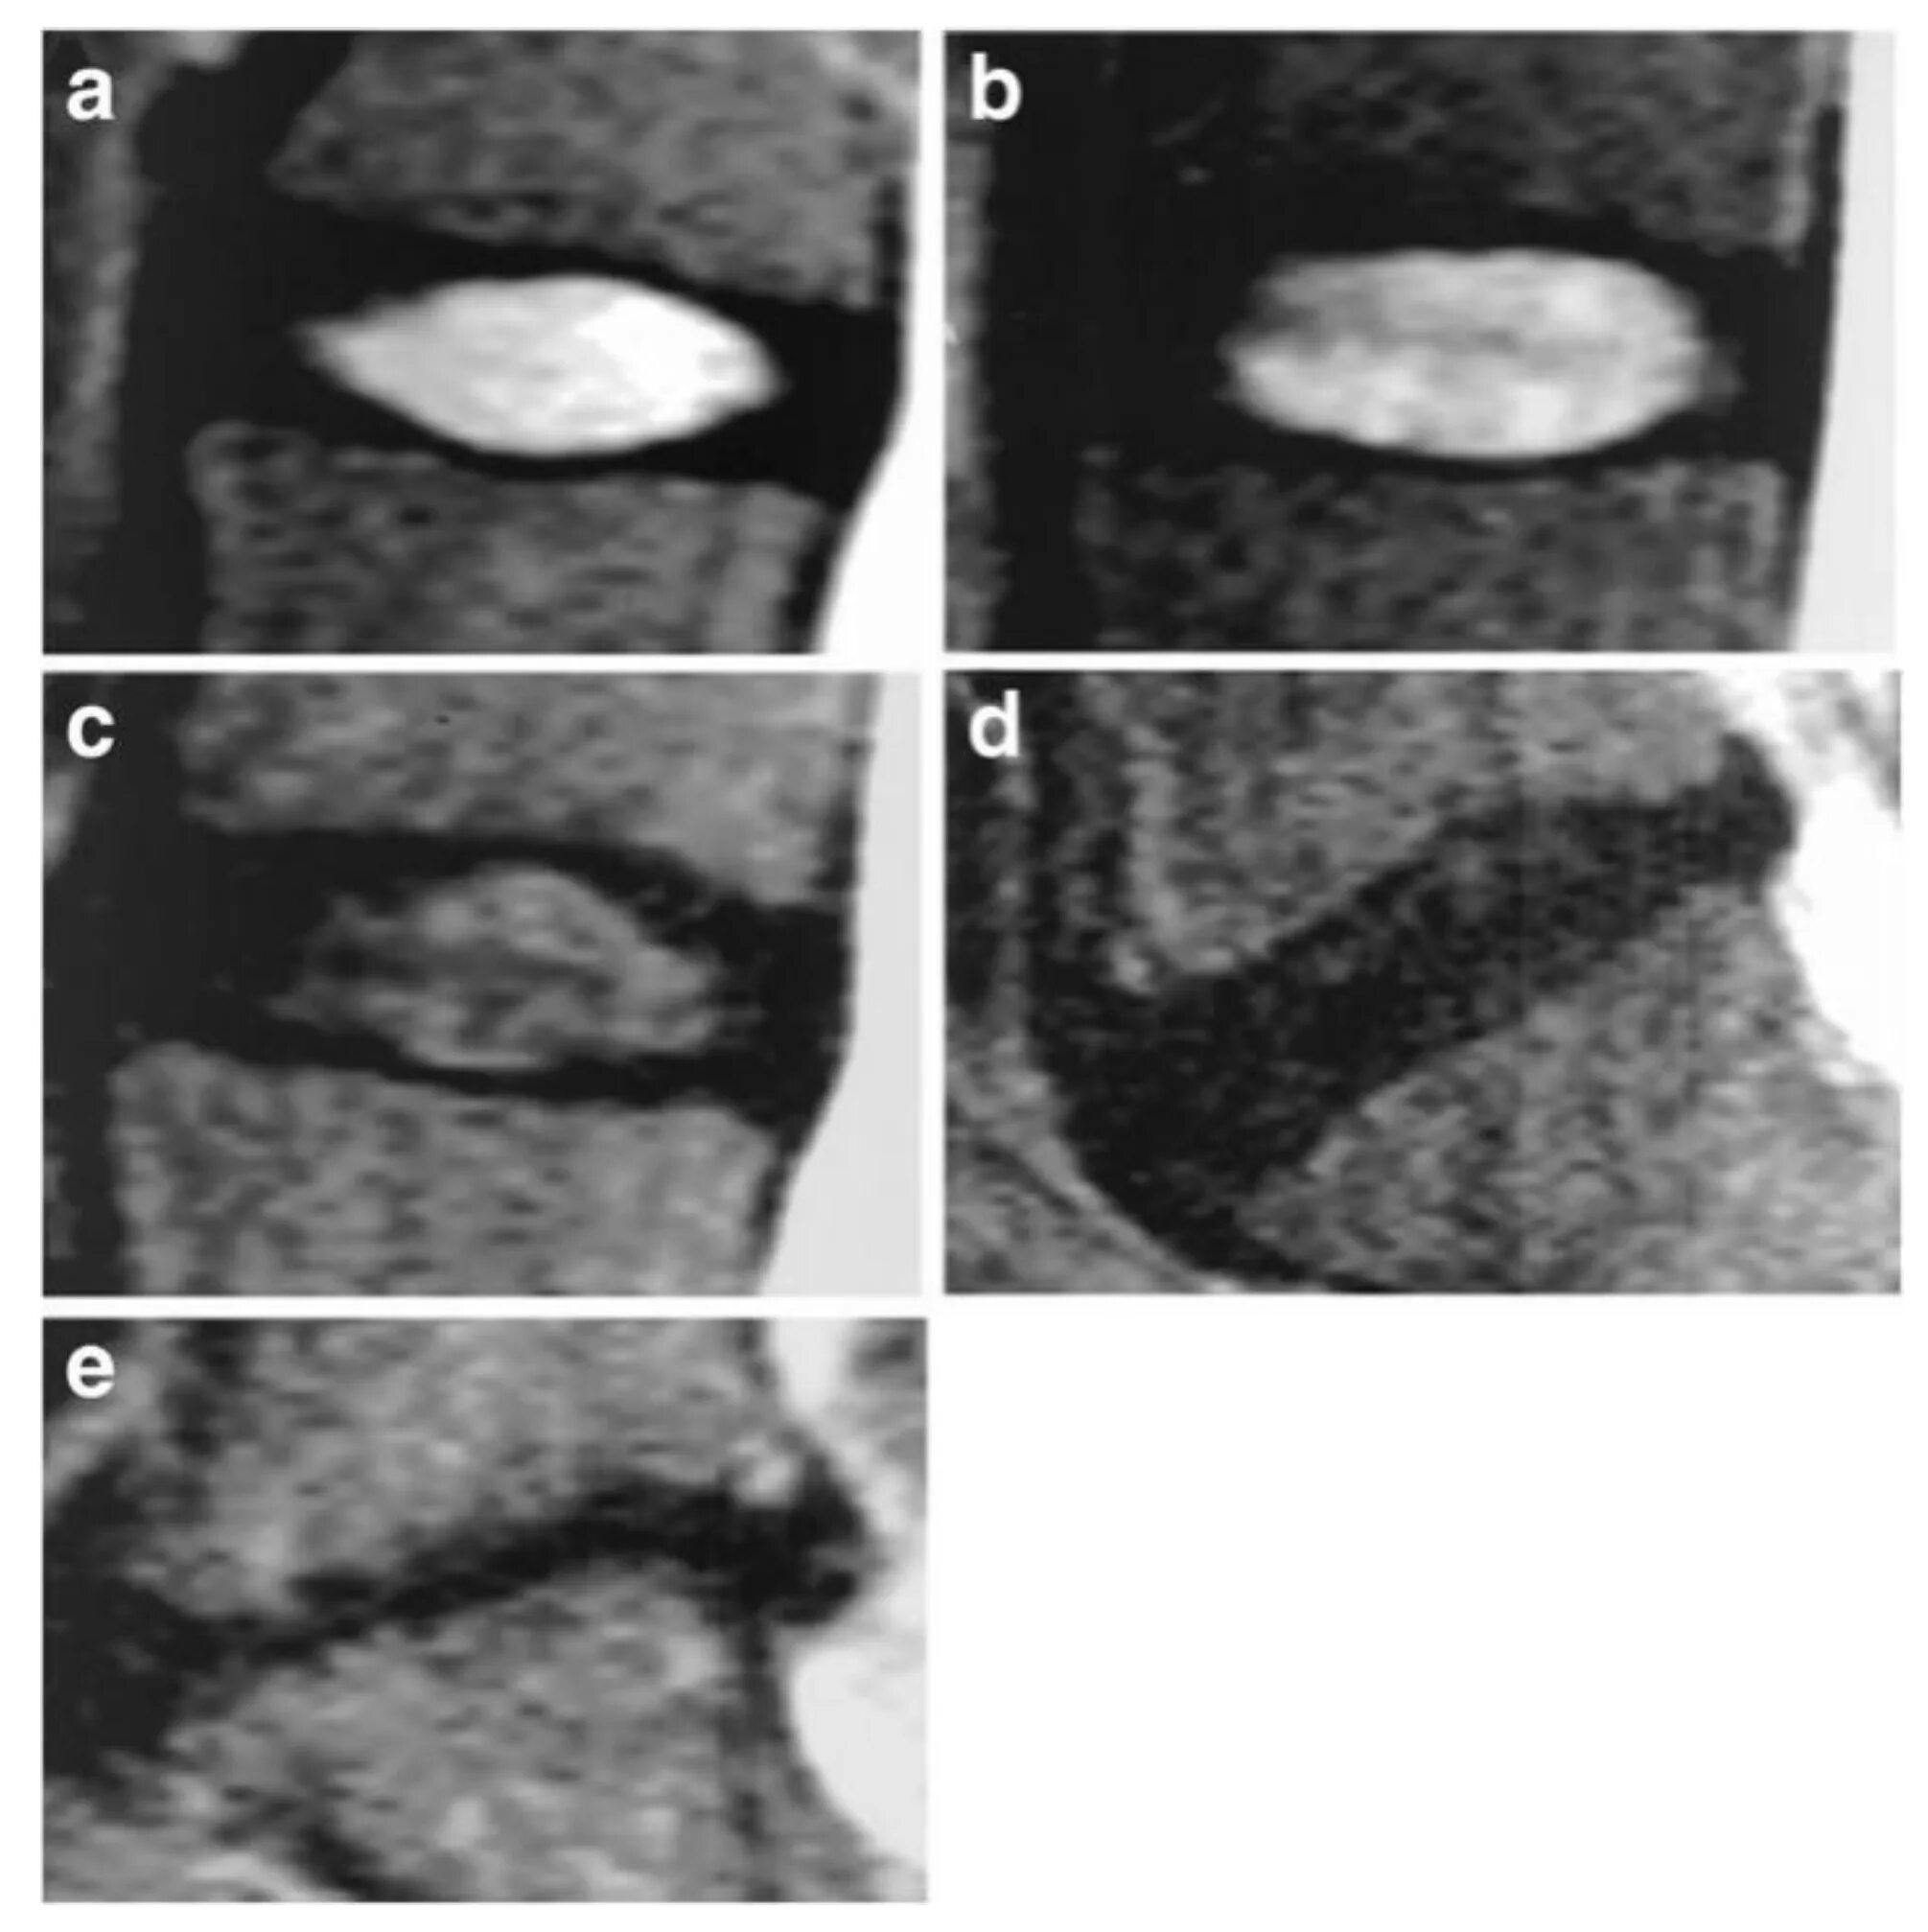

Дегенерация межпозвонкового диска по pfirrmann